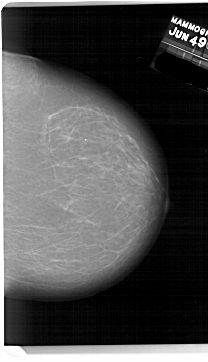

A_1639_1.LEFT_MLO

LEFT_MLO LINES 5956 PIXELS_PER_LINE 3496 BITS_PER_PIXEL 12 RESOLUTION 43.5 OVERLAY